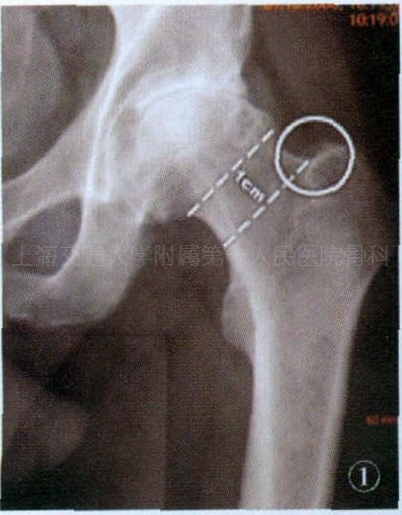

图1 术前X线片测量截骨部位

与其他手术入路一样,DAA术前需要常规进行测量和试模,以决定使用的假体种类和型号。唯一与其他入路不同的是,DAA在进行股骨颈截骨时不脱位髋关节,这需要术前精确定位和测量。术前可在前后位X线片上找到大粗隆与股骨颈移行处作为截骨的起始点。为了更容易地取出股骨头,建议作相距1cm的两道股骨颈截骨(即在初始截骨部位远端1cm处再平行截骨,见图1)。当取出1cm厚度截骨块后,股骨头便容易取出。